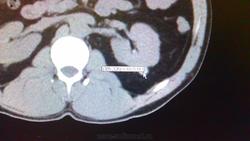

Вы серъезно  хотите по этим картинкам получить  адекватное заключение?Вижу субкапсулярную кисту левой почки.

Если это не кальцинат, то киста с кровоизлиянием. А цель исследования какова? Жалобы? Клиника?

Извините за качество, жалоб нет, открылся кабинет МРТ-решили посм-ть Главного- написали ( мрт)образования левой почки-гипертрофия почечных столб.-рекомендовали кт с ку, гл. врач сам уролог, приш. в кт-начались проблеммы, при исследовании треснула колба( всего обрызгали контрастом)-недостаточно к.в., он сам решил , что у него рак, я написала гиперденсивные кисты(осложн)( высокое содержание белка ? кровоизл?), смущало то, что на кт образования в нативе гиперденсивные , а мрт пишут изоденсивны почечной паренхиме.Спасибо

Изоденсивными на МРТ быть не могут, только изоинтенсивными чему-то на какой-то импульсной последовательности или на всех. Уж кисты почек на МРТ смотреть - лучше не придумать.